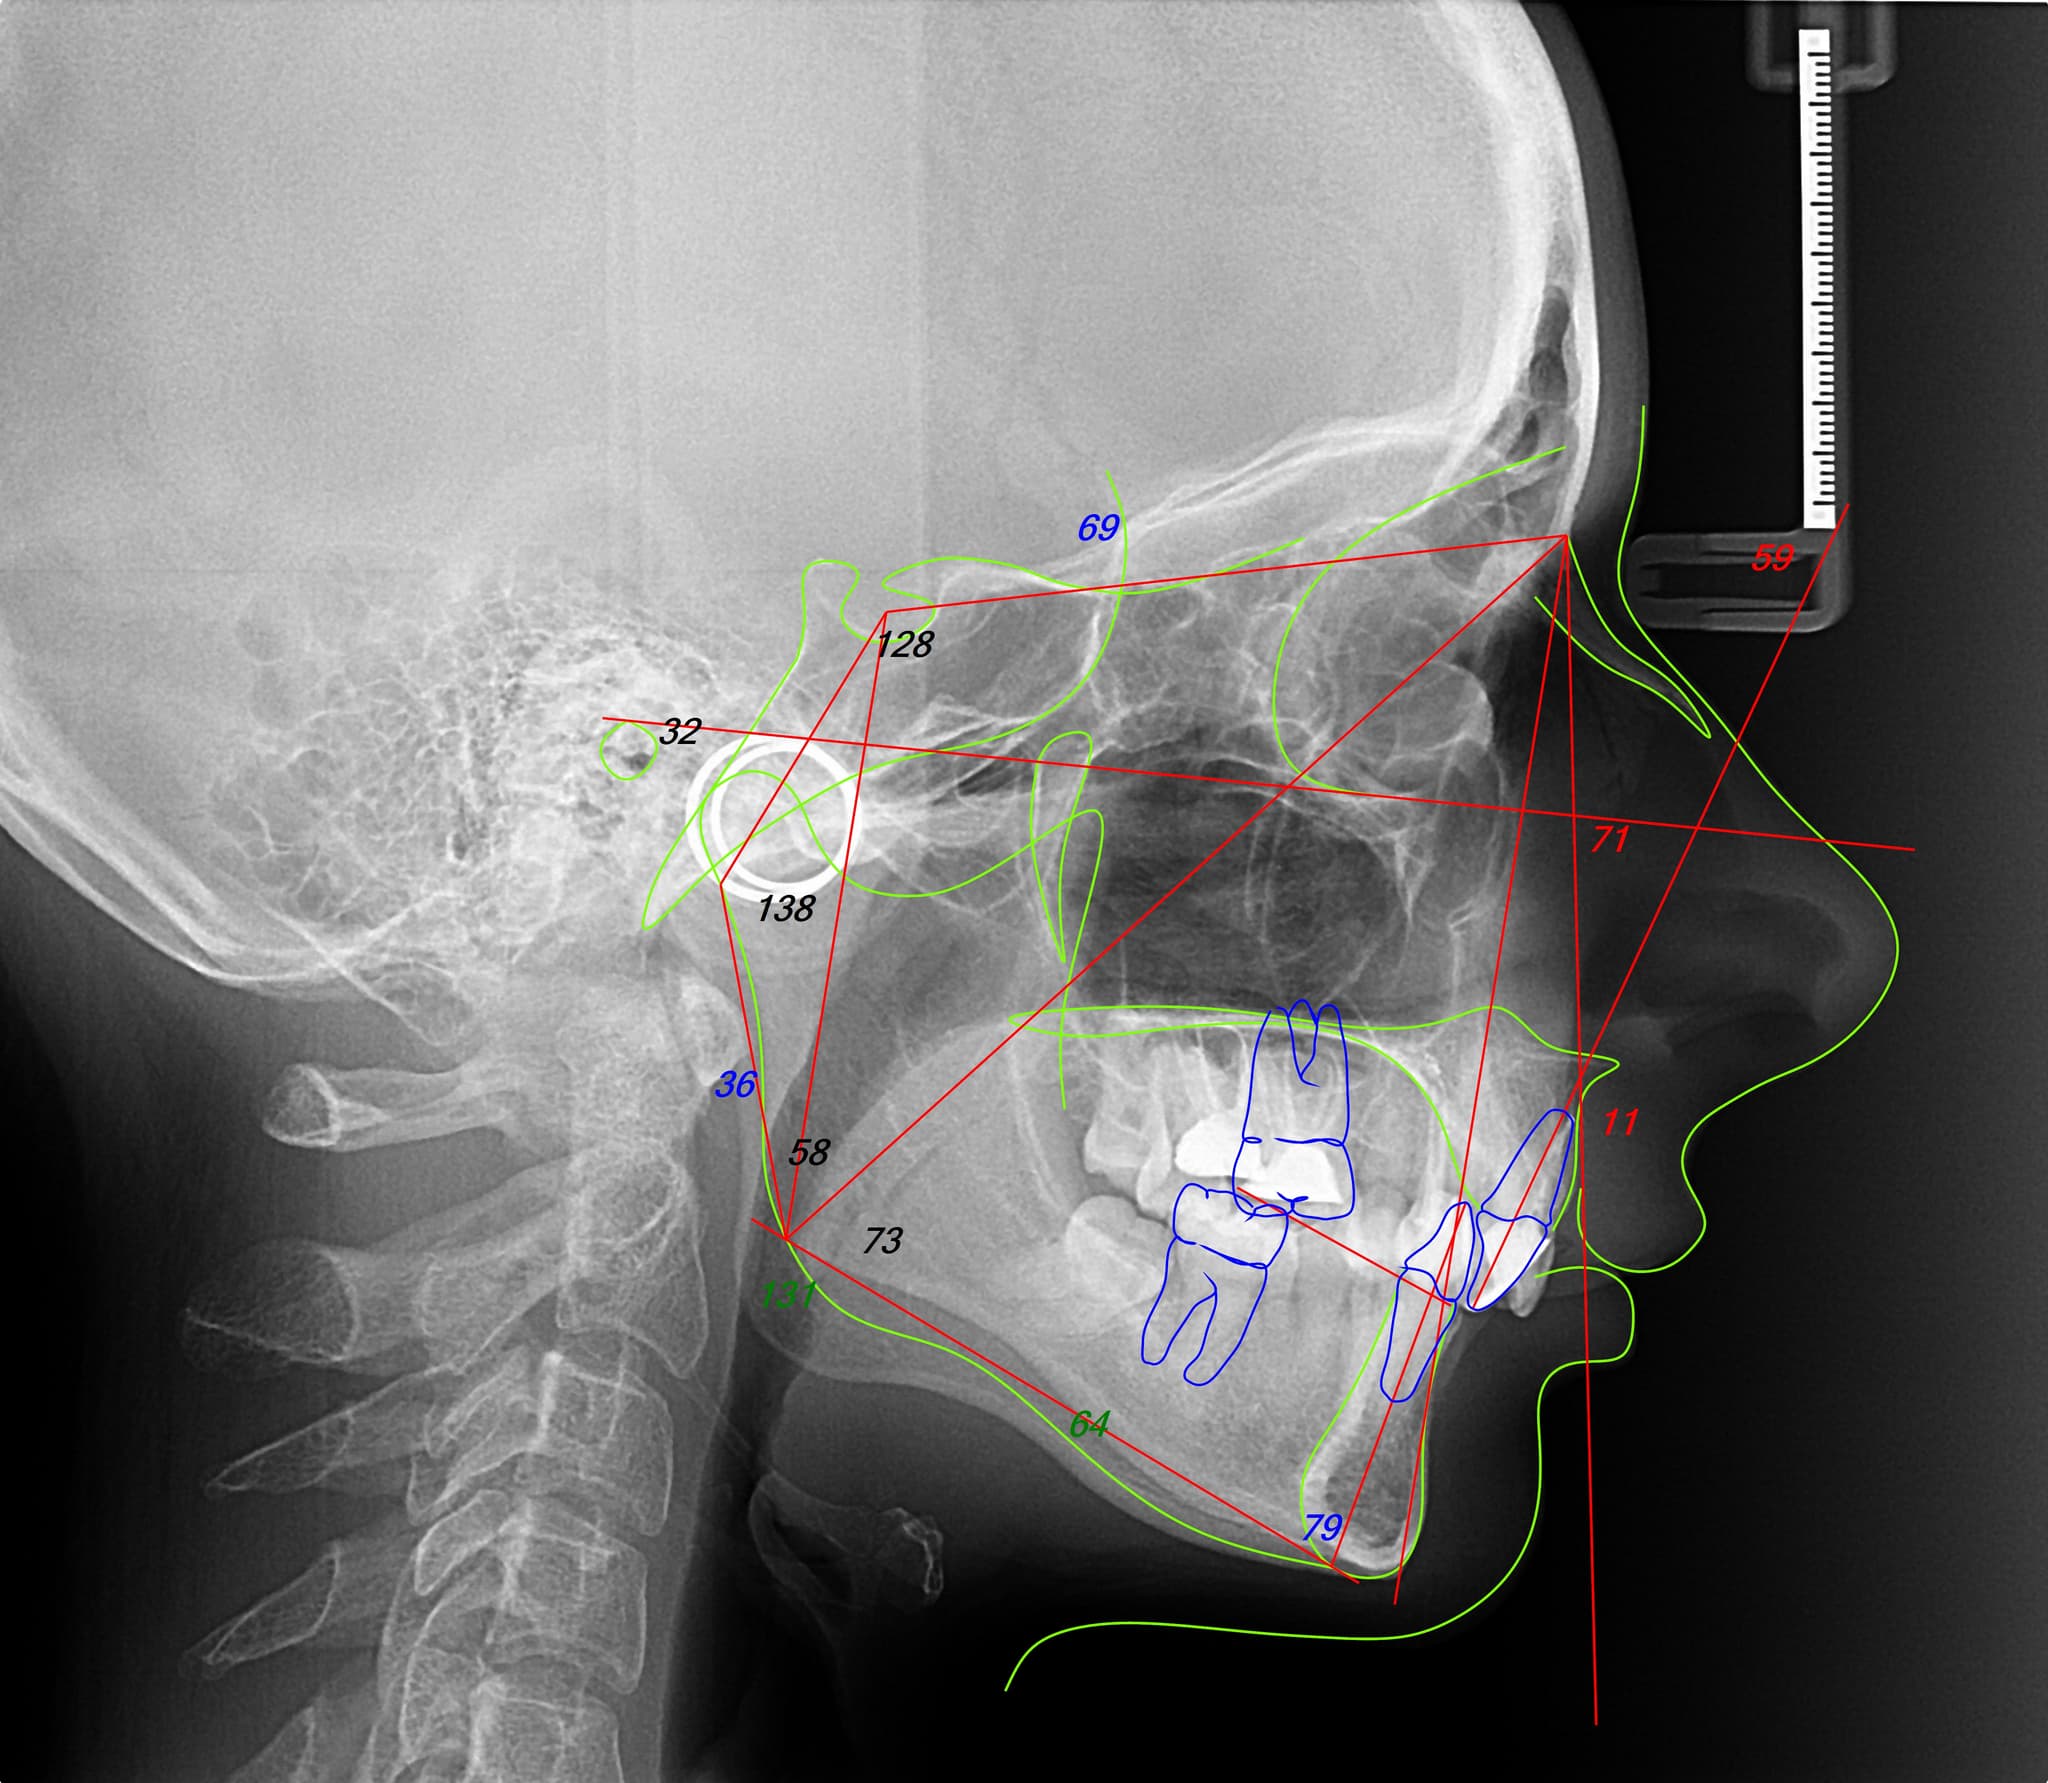

Fiecare caz ortodontic începe cu o analiză digitală completă: fotografii faciale, scanări ale ocluziei și poziția mandibulei. Pe baza acestor date, construim un plan unic interdisciplinar, aliniind ortodonția cu obiectivele generale ale tratamentului—fie ele protetice, chirurgicale sau parodontale. Această abordare stratificată, dar unitară, asigură că fiecare mișcare contribuie la un rezultat coerent și sustenabil.

Nu tratăm niciodată dinții izolat. Structura feței, expresiile și dinamica musculară definesc întregul plan ortodontic. Acest lucru ne permite să mișcăm dinții cu intenție, urmărind armonia, nu perfecțiunea mecanică.